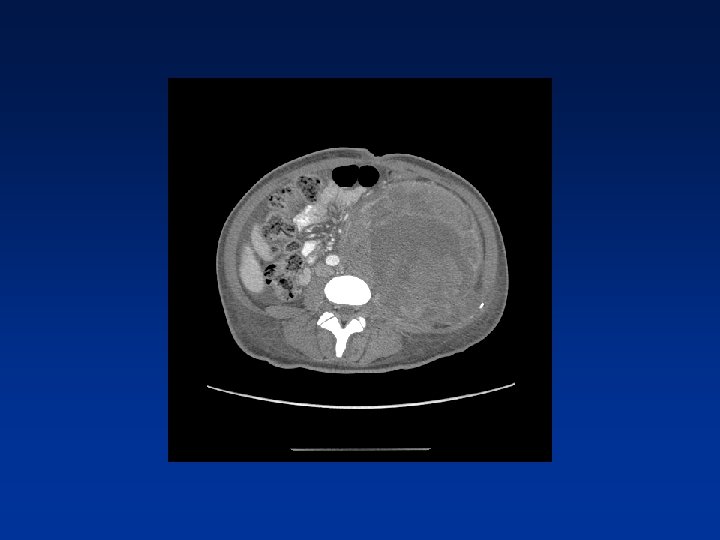

CASE